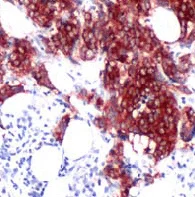

Immunohistochemistry (Formalin/PFA-fixed paraffin-embedded sections) - Anti-Tau antibody [SP70] (AB93726)

ab93726 at 1/100 dilution staining Tau in formalin-fixed, paraffin-embedded Human breast carcinoma tissue.

Immunohistochemistry (Formalin/PFA-fixed paraffin-embedded sections) analysis of Human breast carcinoma tissue sections labeling Tau with ab93726 at 1/100 dilution (1.24 μg/ml). Heat mediated antigen retrieval with sodium citrate buffer (pH 6.0, epitope retrieval solution 1) for 10mins. Rabbit specific IHC polymer detection kit HRP/DAB (ab209101) was used as the secondary antibody. Hematoxylin was used as a counterstain. Cytoplasmic staining on human breast carcinoma, performed on a Leica Biosystems BOND™ RX instrument.

The section was incubated with ab93726 for 30 mins at room temperature.